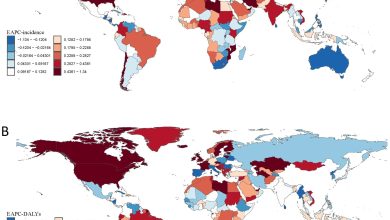

O número de mortos por drogas mais que dobrou em todo o mundo nas últimas três décadas, o estudo encontra

Distribuição espacial global da alteração percentual anual estimada (EAPC) em transtornos de uso de drogas (DUD), 1990-2021. (A) EAPC em…